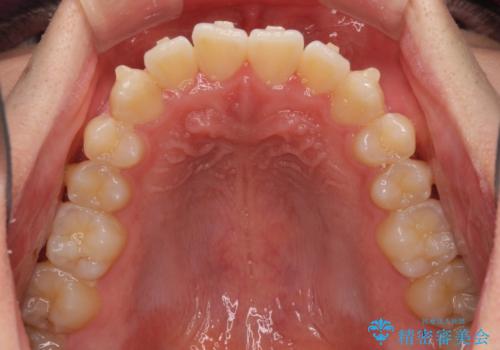

- 上下前歯のデコボコを気にして来院された患者様です。

叢生は軽微であり、費用を抑えて期間もあまりかけずに治療をしたいとのことで、インビザライン・ライトを用いて矯正治療を行うこととしました。

途中通院できなくなり、マウスピースの装着もしっかりとできなかったため、治療期間が長くかかってしまいました。